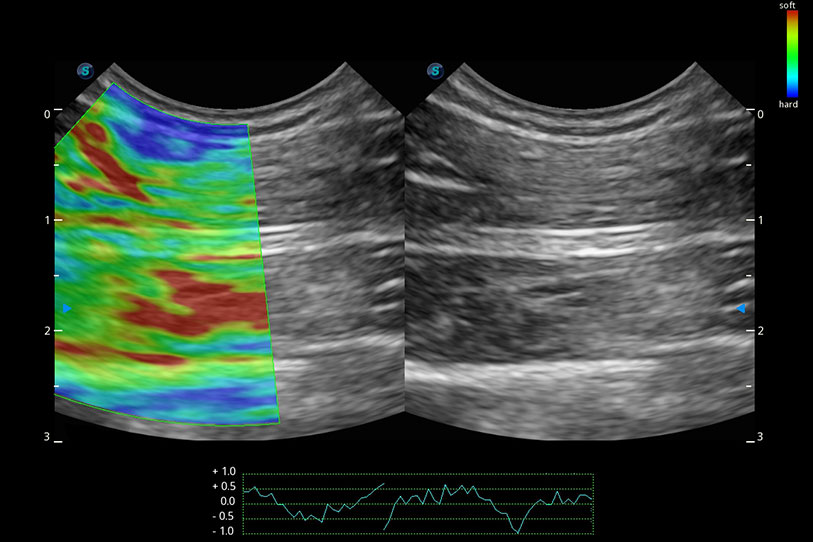

操作簡便,無需高頻度外力作用即可真實(shí)反映組織的形變,快速評估腫瘤良惡性。

采用紅、橙、黃、綠、青、藍(lán)、紫這七種肉眼最為敏感的色彩,直觀地顯示組織內(nèi)血流灌注的時(shí)間先后信息,更精準(zhǔn)捕捉血流灌注走行細(xì)節(jié)。